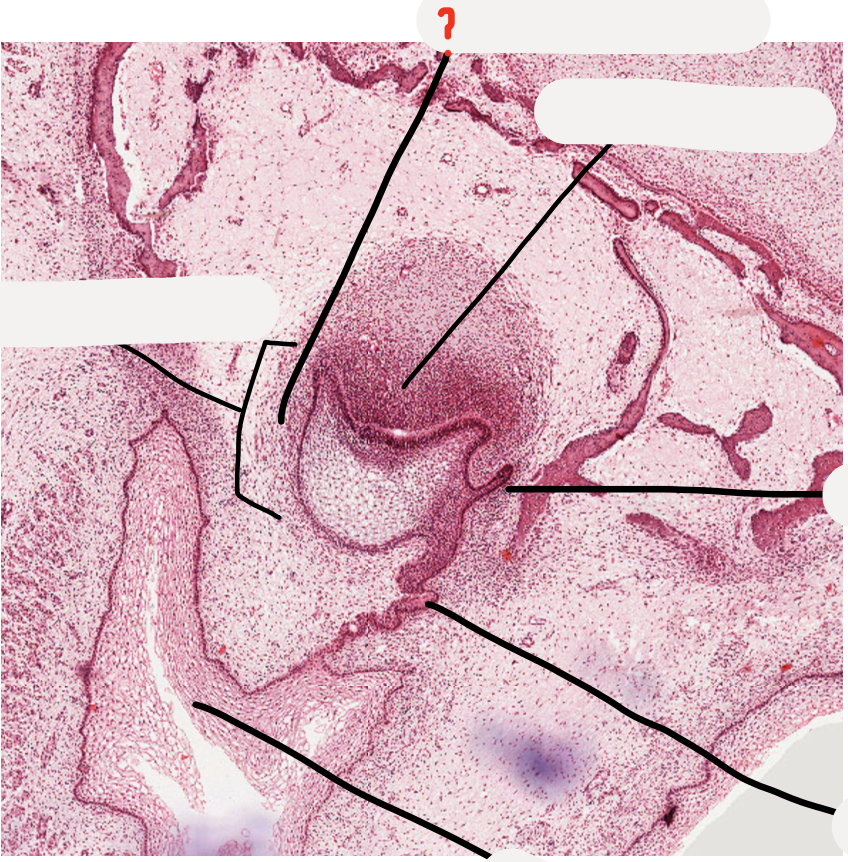

19

Q

A

inner enamel epithelium

20

stratum intermedium

21

successional lamina

22

stellate reticulum

23

outer enamel epithelium